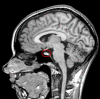

Case presentation: A 65-year-old Caucasian woman with lethargy, loss of appetite and peripheral edema was found to have anterior hypopituitarism. Magnetic resonance imaging showed no mass lesions in the pituitary although a positron emission tomography scan showed abnormal pituitary activity. An abdominal computed tomography scan revealed multiple intra-abdominal lymph nodes, which on histology proved diagnostic of diffuse large B-cell non Hodgkin's lymphoma. She received six cycles of R-CHOP chemotherapy, after which she achieved a complete metabolic response at all known previous sites of the disease, confirmed by positron emission tomography scanning. Concomitant with the tumor response, there was full recovery of adrenal, thyroid and gonadal axes which has persisted at 10 months follow-up.